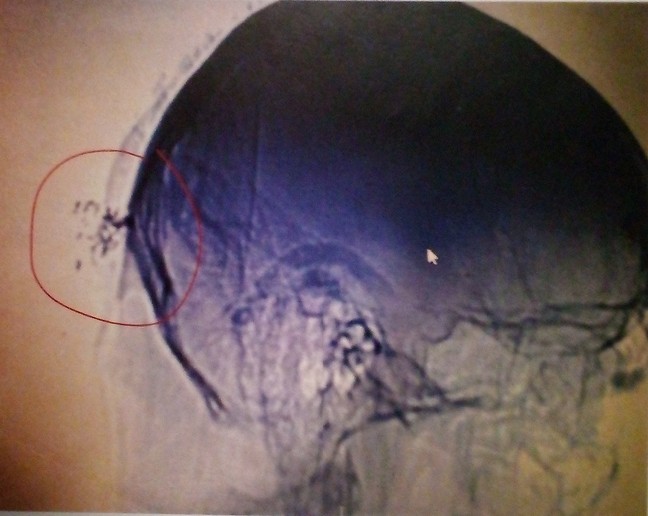

The most vulnerable area of the head:

The temple is where the frontal, parietal, temporal, and sphenoid bones meet, creating a weak point in the skull.

The middle meningeal artery, which supplies blood to the brain, lies directly under this thin bone. A strong blow can fracture the bone and rupture the artery, leading to blood collecting between the skull and brain (epidural hematoma), causing severe pressure and potential brain damage or death. Other vulnerable areas include the pterion, a thin spot just behind the temple, and the jaw, which can transmit force to the brainstem.

Targeted Individuals are attacked by beams of directed energy while sleeping that heats their brains and causes brain damage.